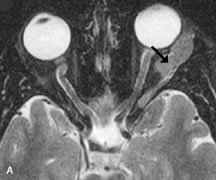

Infectious Disorders

MRI findings of preseptal and orbital cellulitis typically include increased signal intensities on T2-weighted images of the eyelids and orbital fat, respectively, due to the increased water content of the tissues. Since most cases of bacterial orbital cellulitis are associated with paranasal sinusitis, hyperintense signals of the affected sinuses may also be found on T2-weighted images as well as enhancement of polyps and granulation tissue on postgadolinium T1-weighted MR images. Subperiosteal abscess formation may occur due to contiguous spread of infection from the paranasal sinuses and appear on MRI as an area of intermediate signal on T1-weighted and proton-weighted MR images. The abscess may appear slightly hyperintense compared with muscle on T2-weighted scans with the necrotic contents having the greatest intensity.67

MRI and MRV are more sensitive than CT in revealing cavernous sinus thrombosis. Engorgement of the cavernous sinus, extraocular muscles, and ophthalmic veins is seen with hyperintensity of the thrombosed sinuses evident on all pulse sequences. The enlarged, thrombosed superior ophthalmic vein appears less hypointense than the normal contralateral ophthalmic vein, and hyperintensity within the lumen of the vessel may be seen on T1- and T2-weighted MR images.68